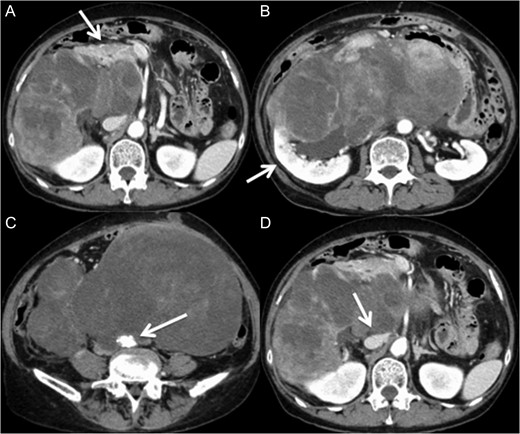

A 60-year-old female visited a clinic because of abdominal distension. She noticed abdominal distention one year prior to her clinical visit, but she left it for a year. Gradual enlargement of the mass eventually made her decide to see a doctor. Enhanced abdominal computed tomography (CT) revealed large retroperitoneal tumors. Mini-laparotomy and tumor biopsy confirmed her diagnosis as dedifferentiated liposarcoma, then she was referred to us for further examination and treatment. A multidetector CT scan revealed a hypodense mass in the retroperitoneum, with a size of ~30 × 20 cm2. The tumor appeared to invade the duodenum, head of the pancreas, right kidney, IVC and abdominal aorta (Fig. 1). The IVC was almost occluded by the tumor, but venous return from the lower extremities beyond the tumor was observed through collateral veins around the tumor (Fig. 2). The tumor invaded the abdominal aorta just below the left renal artery to the common iliac artery bifurcation, although the root and entire length of SMA appeared to be free from the tumor (Fig. 3). She underwent en bloc resection of the RL with resection of the right kidney, duodenum, head of the pancreas, a portion of the inferior IVC and abdominal aorta. Ax-F & F-F bypass was performed for vascular reconstruction using poly-tertrafluoroethylene (PTFE) to maintain the blood flow to the both lower extremities (Fig. 4). The lower abdominal aorta and both sides of common iliac arteries were resected with the tumor. The proximal stump of the abdominal aorta was closed with a running suture and covered by the omentum. The IVC was resected from just below the left renal vein to the common iliac veins. Reconstruction of the venous system including IVC and common iliac veins was not performed because venous collateral pathways had already developed sufficiently. Child’s reconstruction was performed after pylorus-preserving pancreatoduodenectomy. The duration of the surgery was 19 h 22 min, and blood loss was 4 811 mL, requiring 1680 mL of red blood cell transfusion. The tumor was 33 × 20 × 13 cm3 in size, weighed 4800 g, and had a fibrous capsule (Figs 5 and 6). Pathological examination revealed a dedifferentiated liposarcoma with negative margin (Fig. 7). Tumor invaded the pancreatic capsule, the renal capsule, the adventitia of the IVC and the abdominal aorta and infiltrated into the muscularis propria and focally into lamina propria of the duodenum. Edema of the both lower extremities was noted as postoperative complication, but that was gradually resolved by diuretics. The patient was discharged 37 days after surgery without serious postoperative complications such as pancreatic fistula, as well as graft infection or obstruction of two bypasses. Currently, she remains alive and well with no evidence of recurrence at 16 months post-operation.

Multidetector CT scan (coronal view). The tumor invaded the IVC from the orifice of the right renal vein and the peripheral IVC was almost fully occluded.